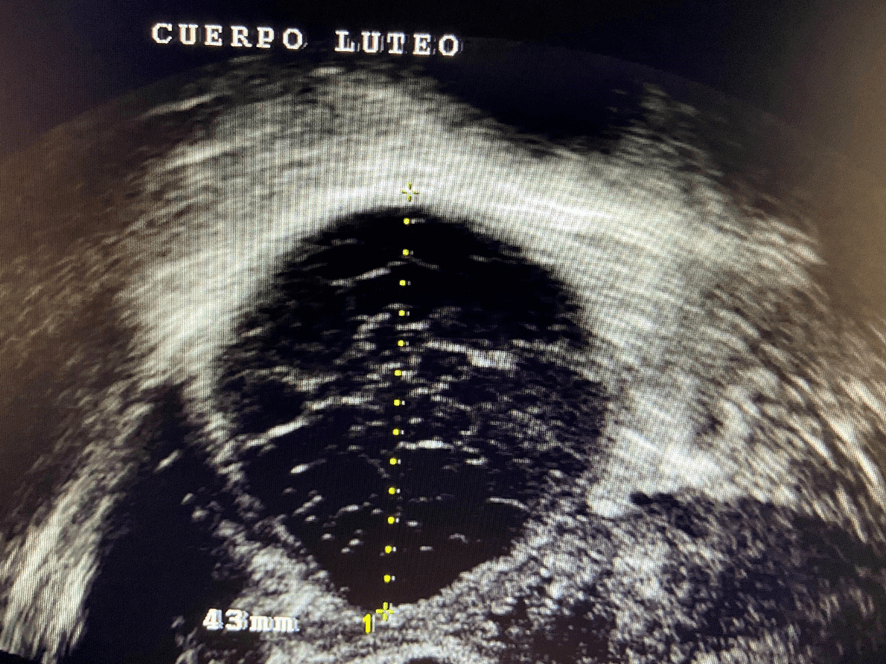

Una vez que el folículo maduro se ha roto -ha estallado- y se ha expulsado el óvulo que contenía (ovulación) la capsula del folículo adquiere un aspecto rugoso, grueso e irregular al que llamamos “cuerpo lúteo”. En su interior, frecuentemente, se produce un acúmulo de sangre por lo que también se le conoce como cuerpo lúteo hemorrágico.

Además de estrógenos, este cuerpo lúteo empieza a segregar una hormona llamada Progesterona; la cual, es la causante de que el endometrio- que antes de la ovulación era proliferativo y con sus tres capas bien definidas- se transforme en un endometrio grueso, espeso e irregular. Se le conoce como “endometrio secretor”.

Una de las formas de identificar al cuerpo lúteo es a través de la imagen ecográfica que obtenemos cuando se le aplica el Eco Doppler Color y aparece el típico anillo de colores que lo rodea.

La producción de estrógenos y sobre todo de Progesterona, por parte del cuerpo lúteo, permanece durante unos 14 días, al cabo de los cuales, si no ha habido embarazo, bajan bruscamente los niveles de estas hormonas y aparece la menstruación. Se desprende y expulsa el endometrio. Empieza así un nuevo ciclo menstrual.